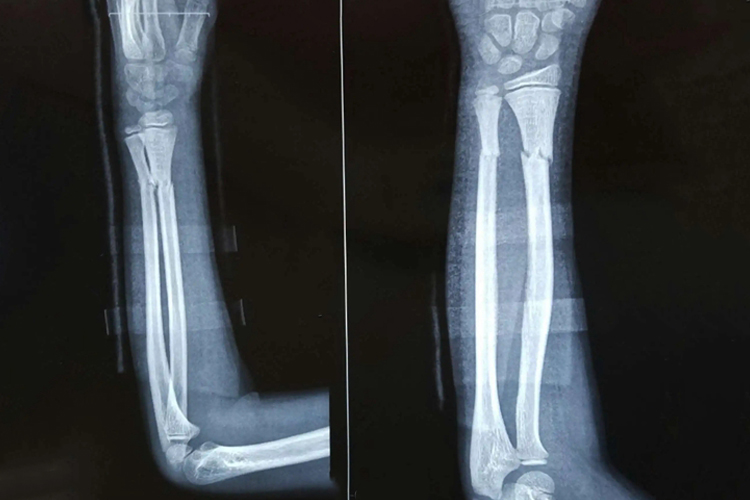

11岁右尺桡骨骨折片子多指X线片,可清楚的显示骨折线,尺桡骨的完整性被破坏,骨折端可无移位。多由直接暴力或间接暴力所致。

11岁右尺桡骨骨折后可通过拍摄X线片来明确骨折类型,常表现为尺、桡骨的连续性中断,见局部有锐利而透明的骨折线,可无移位。严重骨折骨骼常弯曲、变形,骨折线常为严重粉碎或呈多段骨折,常发生移位。

右尺桡骨骨折的X线片表现可以明确损伤机制和所受暴力的程度。低能量损伤的骨折线通常为横断或短斜行,而高能量损伤的骨折线常为严重粉碎或呈多段骨折,常合并广泛的软组织损伤。另外通过右尺桡骨骨折的X线片可以帮助医生进行诊断,并选择合适的治疗方法,对于骨折的治疗和预后有重要影响。